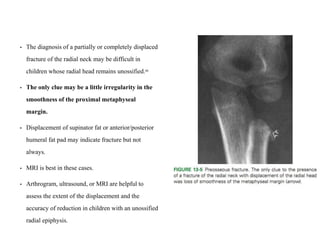

• The diagnosis of a partially or completely displaced

fracture of the radial neck may be difficult in

children whose radial head remains unossified.88

• The only clue may be a little irregularity in the

smoothness of the proximal metaphyseal

margin.

• Displacement of supinator fat or anterior/posterior

humeral fat pad may indicate fracture but not

always.

• MRI is best in these cases.

• Arthrogram, ultrasound, or MRI are helpful to

assess the extent of the displacement and the

accuracy of reduction in children with an unossified

radial epiphysis.